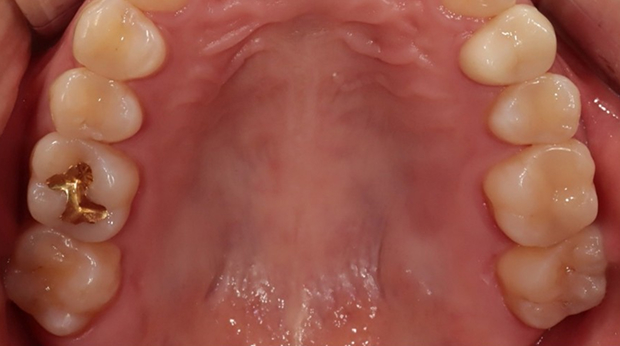

구강외과 진료

라미네이트

고난도 수술 진료